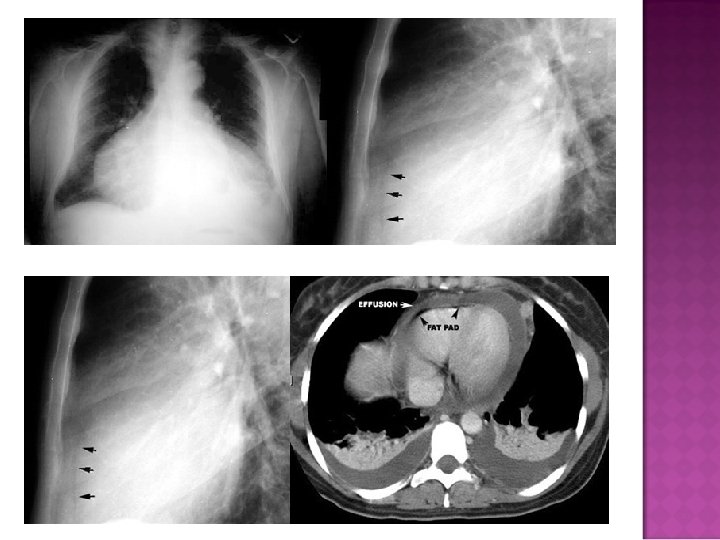

� Sudden inc in size of cardiac silhouette w/o specific chamber enlargement � Effacement of the normal cardiac borders � Development of a “flask” or “H 2 O-bottle” shaped heart

�May have (+) fat pad sign �Separation of mediastinal / retrosternal fat and epicardial fat by > 2 mm

Normal in patients with acute pericarditis unless pericardial effusion is present Enlarged cardiac silhouette Requires 200 cc of fluid